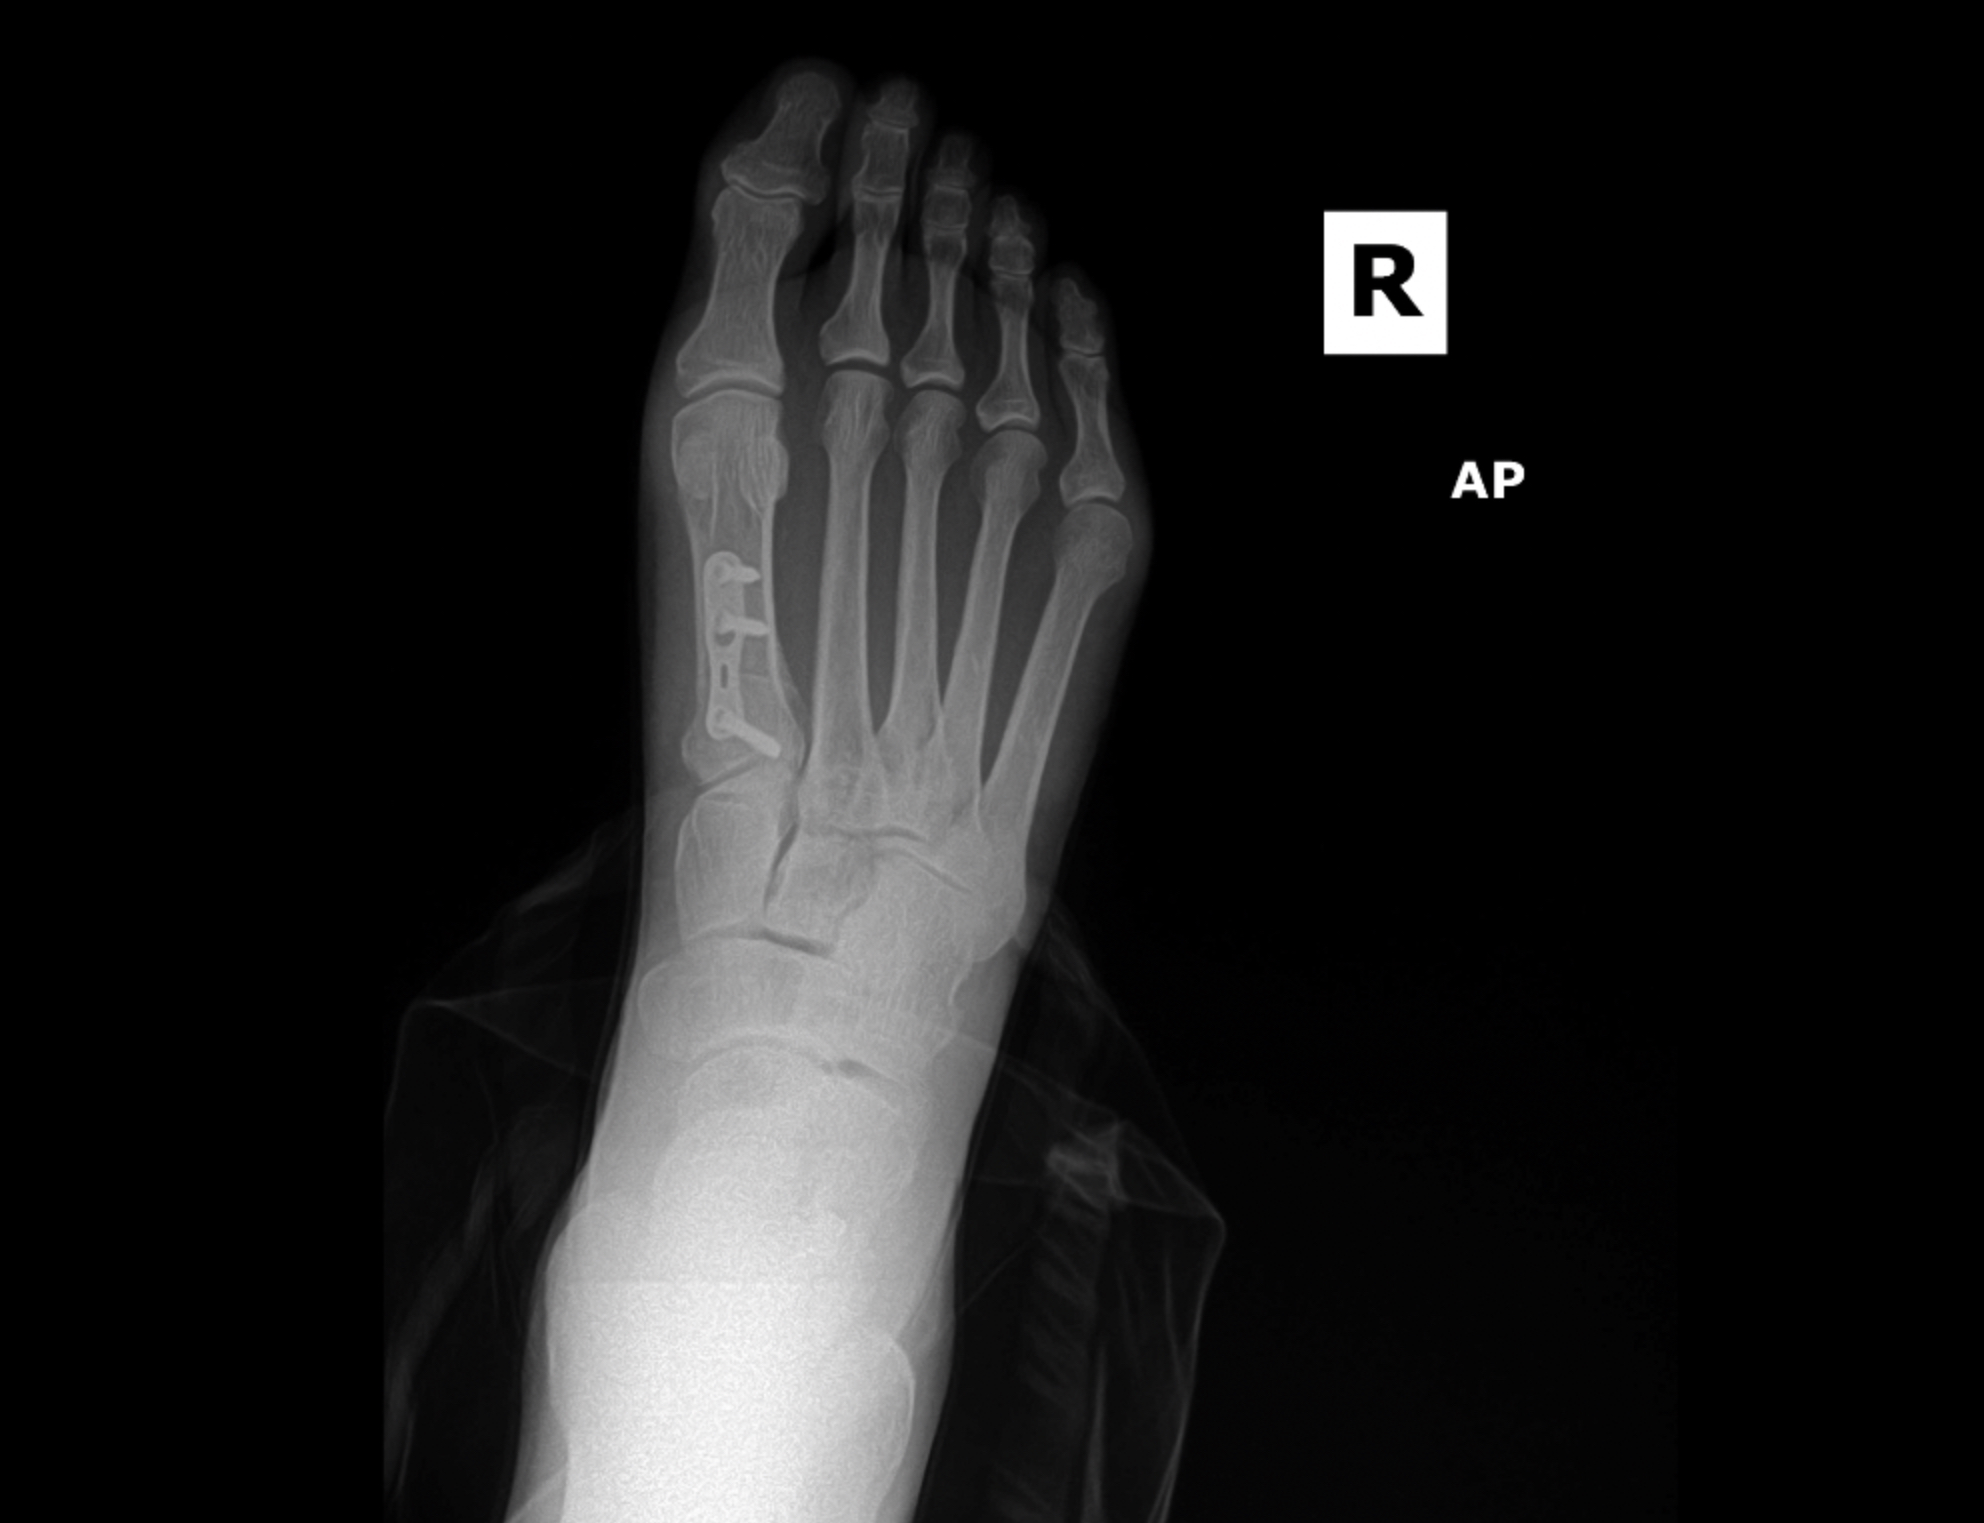

MIS Bunion

MIS3

MIS2